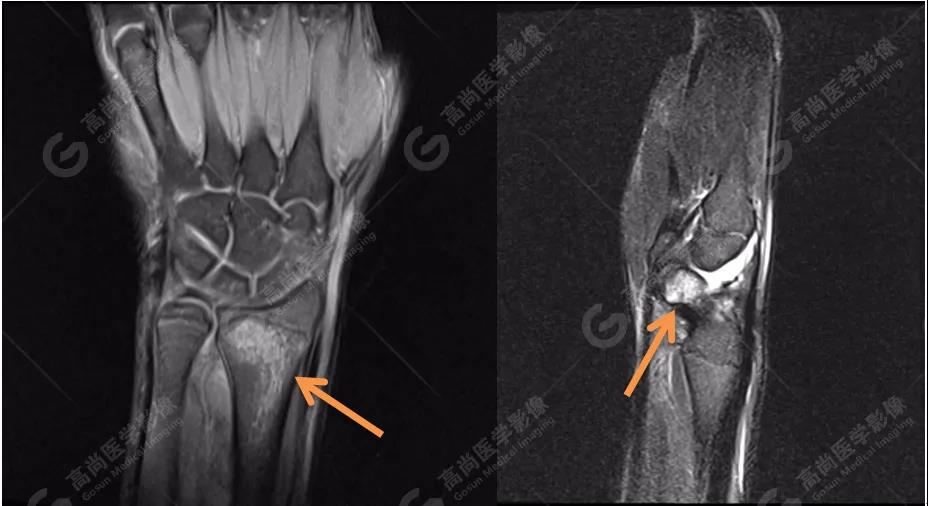

4、MRI圖像

MRI被認(rèn)為是顯示骨髓水腫最好的方法。本著嚴(yán)謹(jǐn)、負(fù)責(zé)的態(tài)度,我們?yōu)椴』济赓M(fèi)行MRI檢查,進(jìn)一步確認(rèn)診斷。

MR質(zhì)子壓脂序列圖像進(jìn)一步證實(shí):左側(cè)橈骨遠(yuǎn)端與右側(cè)舟狀骨骨髓水腫!范圍也與雙能CT骨髓成像圖有很好的吻合度。